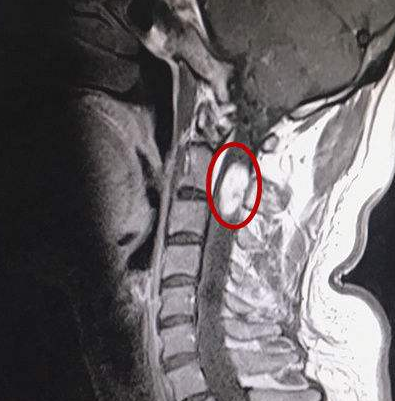

髓内脊髓肿瘤(IMSCTs),如下图所示,是指硬膜内 脊髓肿瘤 的一个亚群,由脊髓内的细胞产生,与相邻结构如神经根或脑膜相对。它们比脑瘤少见得多,据认...

同髓外肿瘤一样,髓内肿瘤也有三种较常见的病理类型,分别为室管膜瘤(30%-40%)、星形细胞瘤(30%-35%)和血管母细胞瘤(2%-15%),共占全部髓内肿瘤的...

什么是脊髓髓内肿瘤? 脊髓肿瘤,又称椎管内肿瘤,是指原发、继发性肿瘤,生长在与脊髓相近的脊髓组织中,包括神经根、硬脊膜、血管、脊髓和脂肪组...